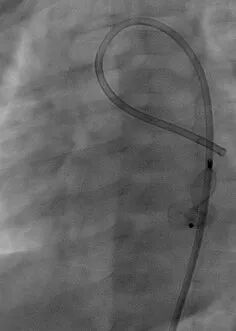

从右侧股动脉引入5F PDA鞘直至瘘口,经鞘管将12 mm的AMPLATZER Plug(AVP Ⅱ)1枚栓塞瘘口。

图片

术后造影示栓塞处少量穿伞分流,前降支通畅,冠状静脉窦通畅。